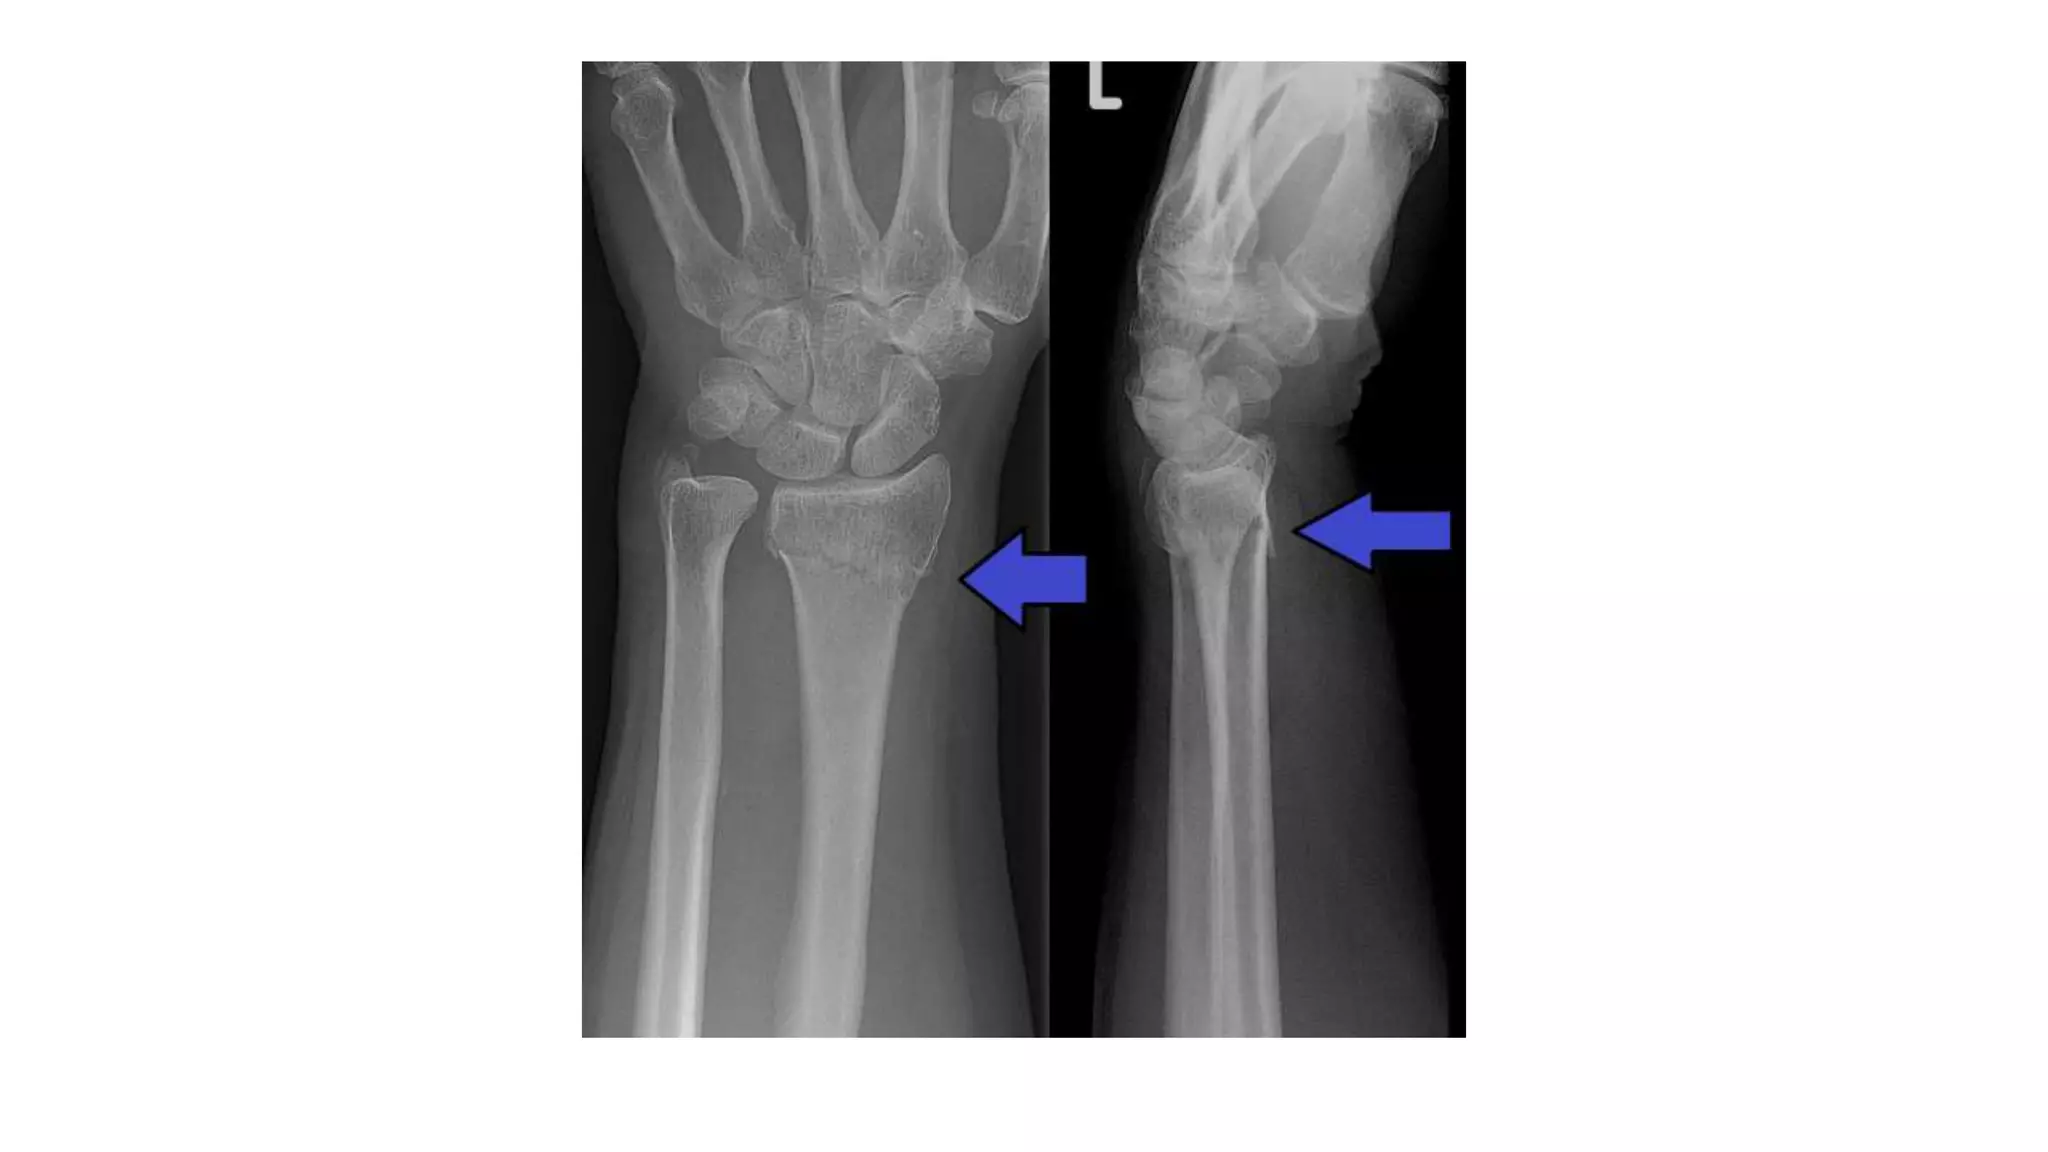

- There is # through the distal radial metaphysis.

- A lateral view shows that the distal fragment is

displaced or tilted anteriorly.

Imaging - There is# through the distal radial metaphysis. - A lateral view shows that the distal fragment is displaced or tilted anteriorly.